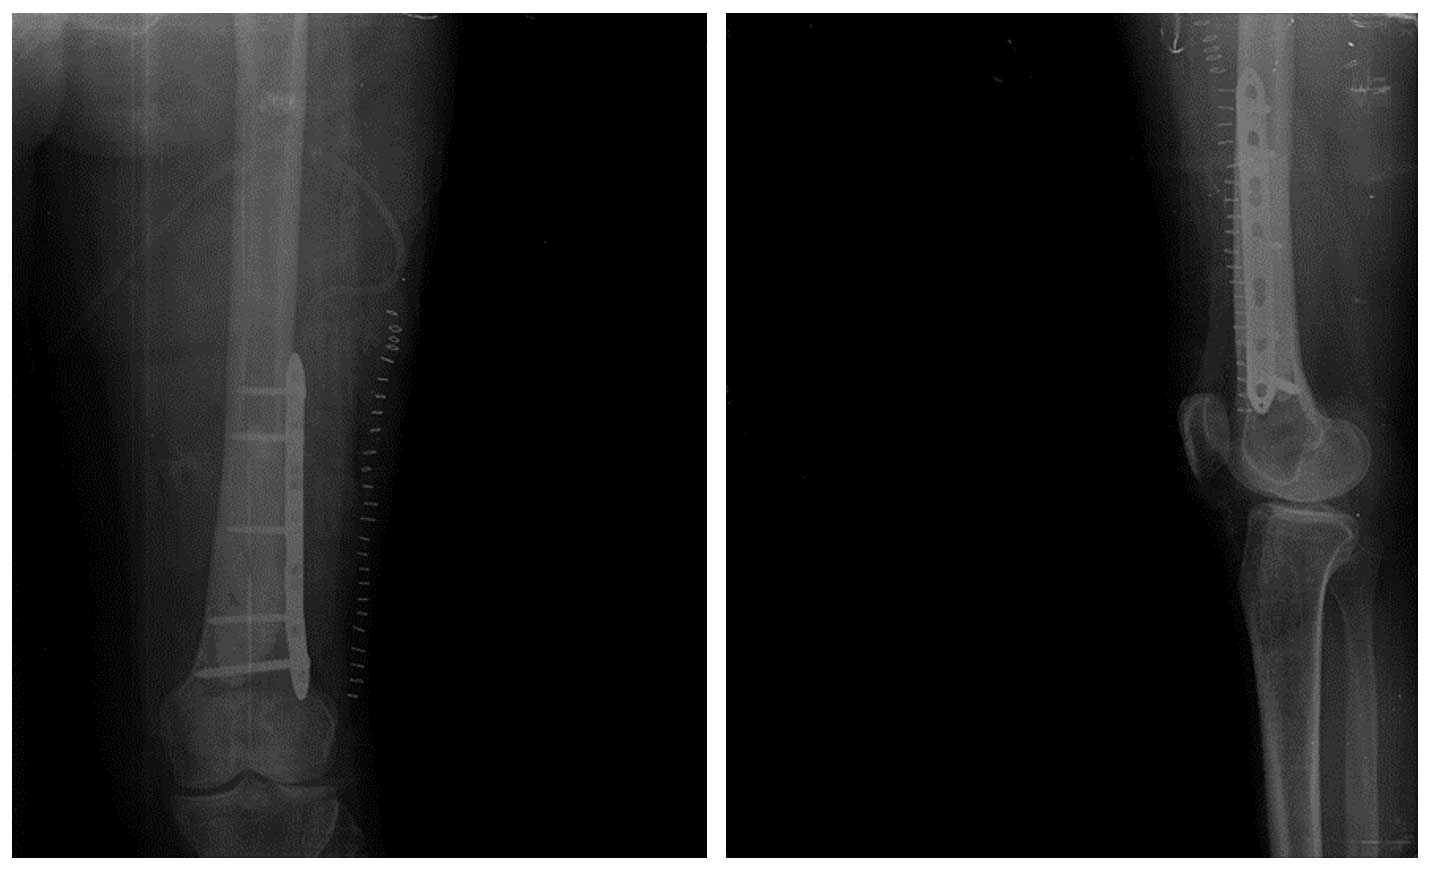

Ameliyat Sonrası: Tümör çıkarıldıktan sonra oluşan boşluğun kemik çimentosu ile doldurulması ve plak ile güçlendirilmesi görülmekte.